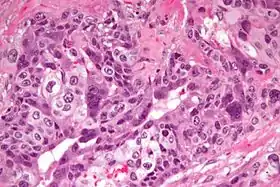

سرطانة مشيمائية

السرطانة المشيمائية (بالإنجليزية: Choriocarcinoma) هي ورم خبيث أرومي غاذي[1] ينشأ عادةً في المشيمة. يعد نوعًا من أورام الخلايا الجرثومية، وقد ينشأ في المبيض أو الخصية.

صورة مجهرية عالية الدقة

صورة مجهرية فائقة الدقة